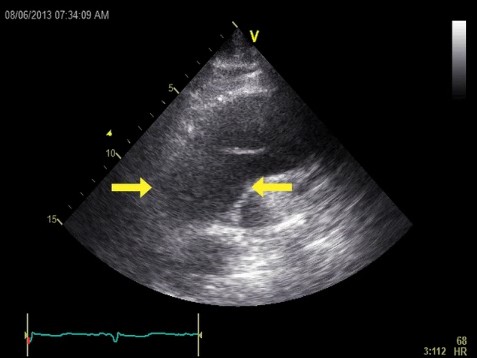

患者男性,81岁,既往无良性前列腺肥大所致耻骨上疼痛及尿潴留的急诊病史。偶然发现肌钙蛋白水平升高:0.17ng/ml(正常值<0.08)。患者称无胸背痛或气促。心电图未显示缺血性改变。胸部X线示纵隔增宽。经胸壁超声心动图示升主动脉水平有一胸主动脉夹层动脉瘤(箭头所示)。